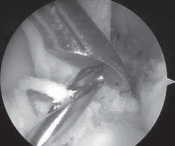

5. In revision ACL reconstruction, the notch often is overgrown and narrow, likely as a result of the previous ACL reconstruction (

TECH FIG 1A

).

1. A notchplasty is completed with use of a 5.5-mm burr, starting at the anterior opening of the notch if necessary.

2. The location of the previous femoral tunnel is noted.

3. Notchplasty is carried back to the posterior wall as needed. A small, curved curette may be used to inspect the back of the notch. A thin white strip of periosteum usually identifies the posterior wall (

TECH

### FIG 1B). Careful attention to localizing the posterior wall is critical, especially because the sides and roof of the notch often are irregular owing to the previous surgery.

1. Anterior placement of the femoral tunnel is the primary cause of recurrent laxity for ACL reconstructions, so in many cases there is enough room to place a second femoral tunnel in the appropriate position without interference or compromise from the previous tunnel. If this is the case, the previous interference screw can be left in place or removed (

TECH FIG 1C,D

TECH FIG 1 • A. Significant overgrowth of the notch noted at the time of revision anterior cruciate ligament (ACL) reconstruction. B. A thin layer of periosteum is easily visualized at the posterior wall of the notch. C. Note the anterior placement of the femoral tunnel interference screw used during the primary ACL reconstruction. The femoral tunnel for the revision can be placed at the appropriate location without removing the interference screw used in the primary procedure. D. The new femoral tunnel and interference screw are placed in the appropriate location without compromise from the screw used in the index procedure. E. View of femoral notch after placement of femoral tunnel and interference screw via anteromedial portal. This allows divergence of the old and new femoral tunnels.